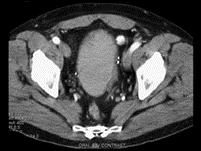

问题 男,55岁,血尿半月余,请根据其影像,判断其最可能的诊断 ( )

选项 A、膀胱憩室伴感染 B、慢性膀胱炎 C、膀胱癌 D、膀胱憩室 E、膀胱结石

答案 C